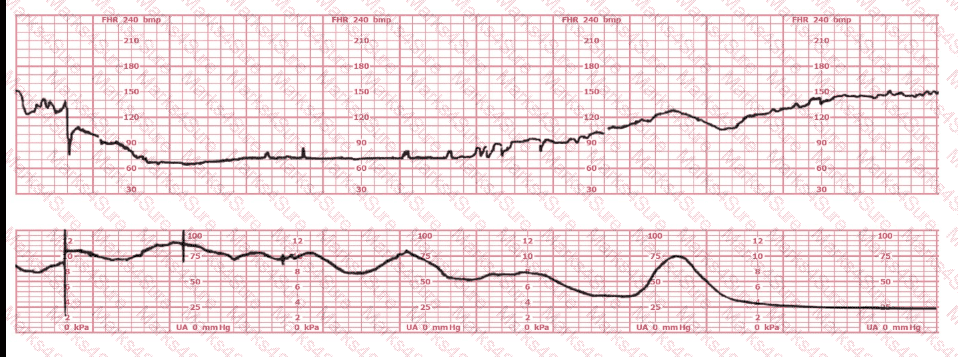

This fetal heart rate tracing is obtained upon the woman's admission to labor and delivery. This tracing is most reflective of: